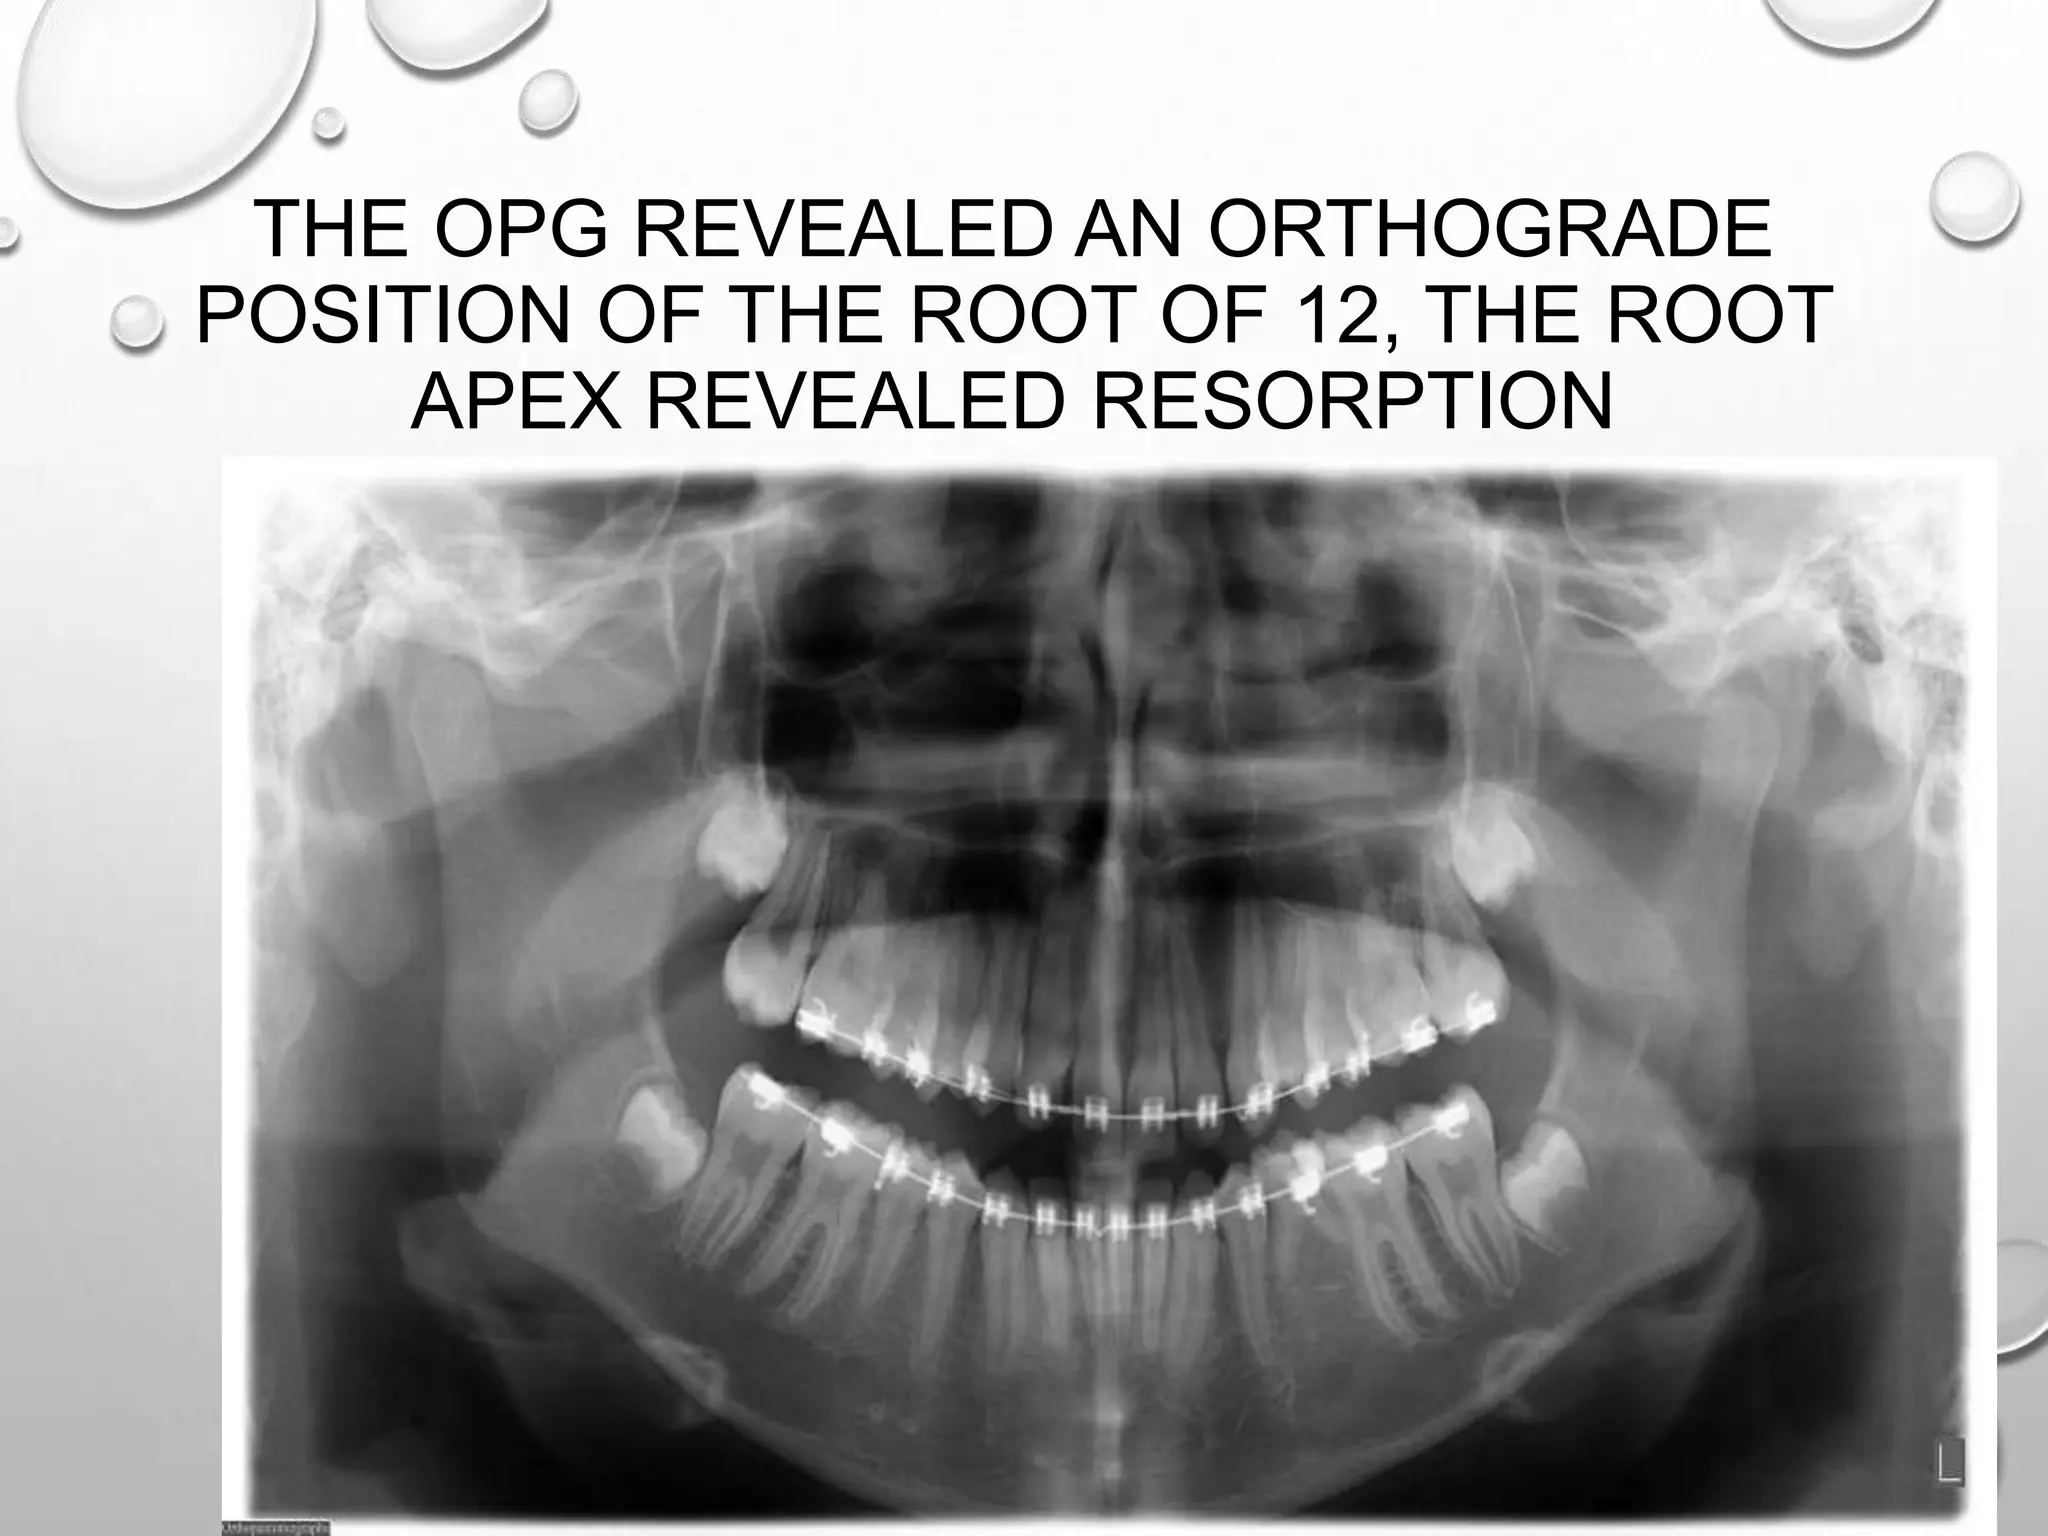

THE OPG REVEALED AN ORTHOGRADE

POSITION OF THE ROOT OF 12, THE ROOT

APEX REVEALED RESORPTION